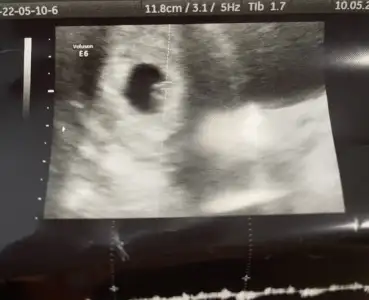

paşa gibi 7 haftalık görüntüsü var mı?Merhaba Nur hanım rica etsem bana da bakar mısınız 9+0 karından![]()

bu görüntü 7-8 haftalık civarı mıSelamPasha22 pazar göndermiştim erkek gibi demiştin. Dün tekrar gittim yeni görüntü var hala erkek mi

![]()